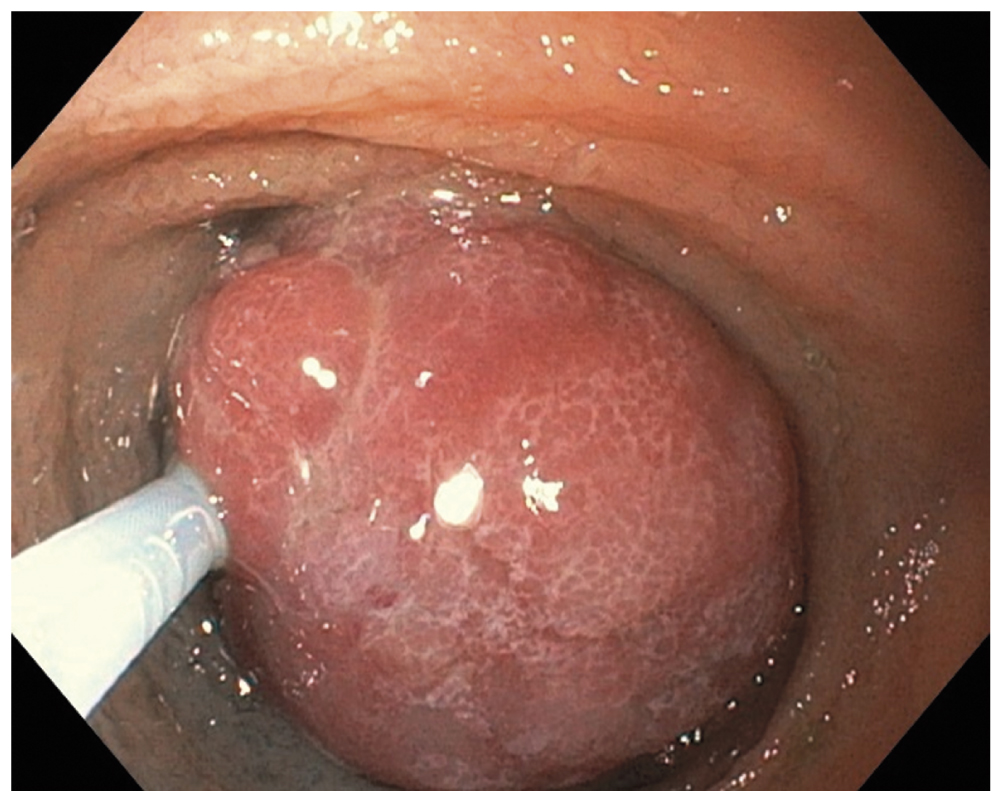

Поскольку в день операции у ребёнка был отмечен очередной эпизод мелены, для исключения поражений Дьелафуа, а также для осмотра тощей кишки на уровне расправленного тонкокишечного инвагината (30–40 см от связки Трейтца) интраоперационным консилиумом принято решение выполнить третье эндоскопическое исследование верхних отделов ЖКТ. В положении ребёнка на левом боку под СО2-инсуффляцией с применением ручного пособия тонкий видеогастроскоп заведён в тощую кишку, где на расстоянии около 40 см от пилорического канала было обнаружено эпителиальное новообразование шаровидной формы размерами 15×17 мм на короткой широкой ножке толщиной около 6 мм (тип 0-Ip по Парижской классификации эпителиальных новообразований) (рис. 6). Поверхность полипа гиперемирована, покрыта единичными округлыми эрозиями с налётом фибрина. Новообразование легко смещалось в просвете кишки при помощи инструментальной пальпации. С целью расширения возможностей инструментария тонкий видеогастроскоп заменён на аппарат стандартного диаметра с рабочим каналом 2,8 мм, который с техническими трудностями, обусловленными малым диаметром просвета ЖКТ у ребёнка, был проведён к новообразованию. Первым этапом с помощью эндоскопического инъектора выполнено введение в подслизистый слой физиологического раствора с индигокарминовым красителем в основание полипа с целью создания гидравлической подушки между слизистой и мышечной оболочками стенки кишки (рис. 7). Отмечен умеренный лифтинг новообразования. Эндоскопической серповидной петлёй Olympus Snare Master 25 мм выполнен захват полиповидного образования в пределах неизменённых тканей и затягивание петли на ножке образования (рис. 8). Выполнено удаление полипа в пределах неизменённых тканей в смешанном режиме коагуляции-резания (электрохирургический блок Olympus) методикой эндоскопической резекции слизистой оболочки. При осмотре после резекции признаков резидуальных тканей новообразования и глубокого повреждения стенки кишки не определялось. Отмечено подтекание крови из ложа удалённого образования. Выполнен гемостаз и сведение краёв дефекта слизистой при помощи трех эндоскопических клипс (рис. 9). Полип извлечён при помощи эндоскопического сачка из просвета ЖКТ и направлен на морфологическое исследование (рис. 10, 11).

Рис. 6. Полип тощей кишки: a — осмотр тонким видеогастроскопом, b — осмотр стандартным видеогастроскопом

Fig. 6. A jejunal polyp: a — image from the thin endoscope, b — image from the standard endoscope